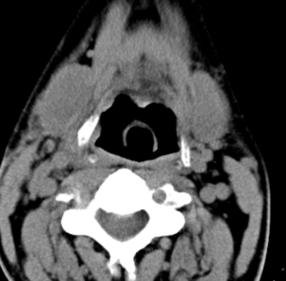

标题: CT17168:会诊,颈部包块 [打印本页]

标题: CT17168:会诊,颈部包块

怎么不传病史呢?右侧颌下腺炎症?

考虑:右侧颌下腺炎症。建议强化。

不排除右侧颌下腺恶性肿瘤可能;建议行进一步检查。

考虑:右侧颌下腺炎症可能。

我也是报的颌下腺炎症。